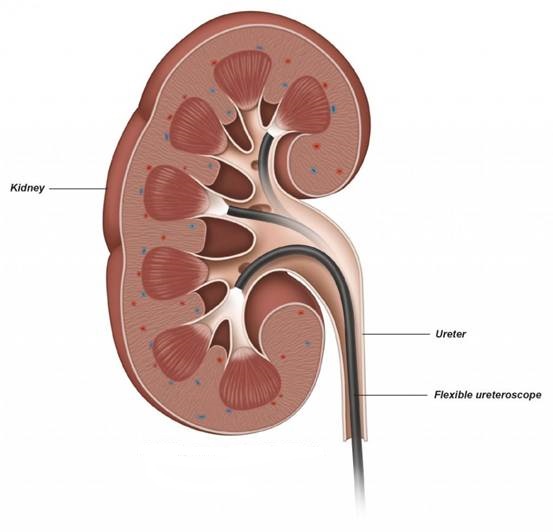

Ουρητηροσκόπηση

Αυτή η επέμβαση χρησιμοποιείται για τη θεραπεία λίθων μικρού έως μεσαίου μεγέθους που βρίσκονται στους νεφρούς και τους ουρητήρες.

Η ουρητηροσκόπηση (Εικ. 2), γίνεται χωρίς τομή στο δέρμα, καθώς τα χειρουργικά εργαλεία περνούν μέσα από την ουρήθρα και την φυσιολογική αποχέτευση του ουροποιητικού συστήματος. Η επέμβαση πραγματοποιείται είτε υπό γενική είτε υπό ραχιαία αναισθησία.

Ο ουρολόγος χρησιμοποιεί ένα λεπτό, εύκαμπτο σωλήνα που ονομάζεται ουρητηροσκόπιο και εισάγεται μέσω της ουρήθρας στην ουροδόχο κύστη, στην συνέχεια στον ουρητήρα και τελικά στο νεφρό. Ο λεπτός αυτός σωλήνας έχει μια μικροσκοπική κάμερα στο άκρο του που χρησιμοποιείται για τον εντοπισμό των λίθων. Τα χειρουργικά εργαλεία (Εικ. 3) όπως η λαβίδα σύλληψης και το basket, περνούν μέσα από ένα ειδικό κανάλι εργασίας του ουρητηροσκοπίου, έτσι ώστε ο γιατρός να μπορεί να αφαιρέσει τυχόν μικρές πέτρες.

Εάν υπάρχουν μεγαλύτερες πέτρες, ο ουρολόγος θα περάσει μια λεπτή ίνα λέιζερ στο εσωτερικό του ουρητηροσκοπίου για να θρυμματίσει τις πέτρες σε μικρότερα κομμάτια τα οποία μπορούν στη συνέχεια να αφαιρεθούν, ή να αφεθούν στη θέση τους, αν είναι πολύ μικρά, ώστε να περάσουν δια της αποχετευτικής οδού, φυσιολογικά κατά την ούρηση.

Μετά τη ουρητηροσκόπηση, μπορεί να χρειαστεί να τοποθετηθεί ένα στέντ (ένας μικρός σωλήνας σιλικόνης) για να κρατήσει τον ουρητήρα ανοιχτό έτσι ώστε να εξασφαλιστεί ότι τα ούρα θα μπορούν να παροχετεύονται ελεύθερα. Αυτά τα στέντ είναι προσωρινά και αφαιρούνται εύκολα μερικές εβδομάδες μετά την επέμβαση.

Εικ. 2: Η εύκαμπτη Ουρητηροσκόπηση